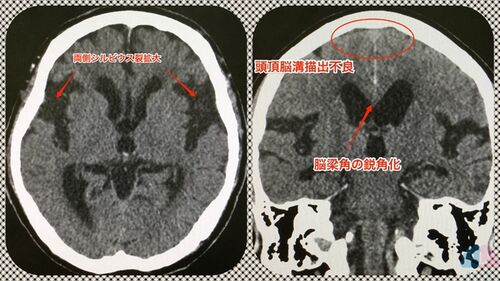

考え方や性格が似ている夫婦を俗に「似たもの夫婦」と呼ぶが、世の中には頭のCT所見が似ているご夫婦もいるということを先日知った。